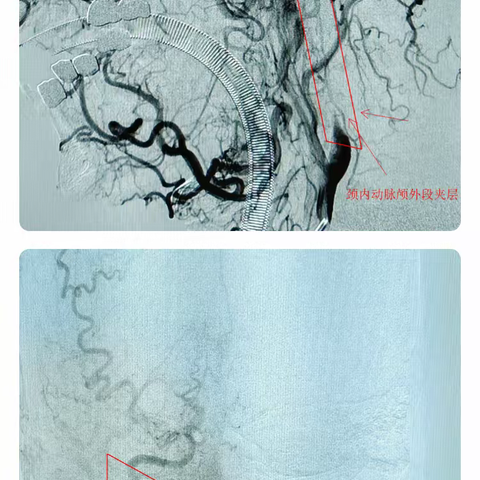

从业以来最难做的一例颈内动脉颅外段夹层----大脑中动脉串联闭塞

年轻患者“眼中风”,罪魁祸首竟然是致命的颈动脉夹层